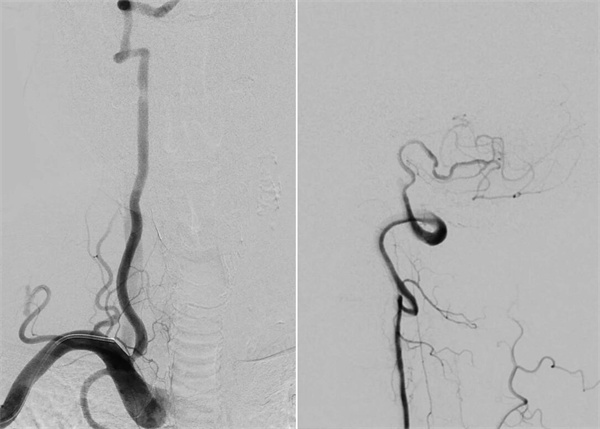

患者高先生,70岁,患有高血压病多年。2年前曾行冠状动脉搭桥术,平素规律服药。2个月前,他因左上肢突然麻木被送至清华大学垂杨柳医院急诊科就诊。头颅CT提示右侧顶叶少量蛛网膜下腔出血。后入住神经外科进一步诊治,全脑血管造影(DSA)结果显示:右侧椎动脉起始部重度狭窄约70%,左侧椎动脉颅内段闭塞;右侧椎动脉颅内段存在大小约3.5×2毫米的夹层动脉瘤;右侧颈内动脉颅外段存在重度狭窄,左侧颈内动脉通过前交通动脉代偿。

▲右侧椎动脉起始重度狭窄,左侧椎动脉颅内段闭塞